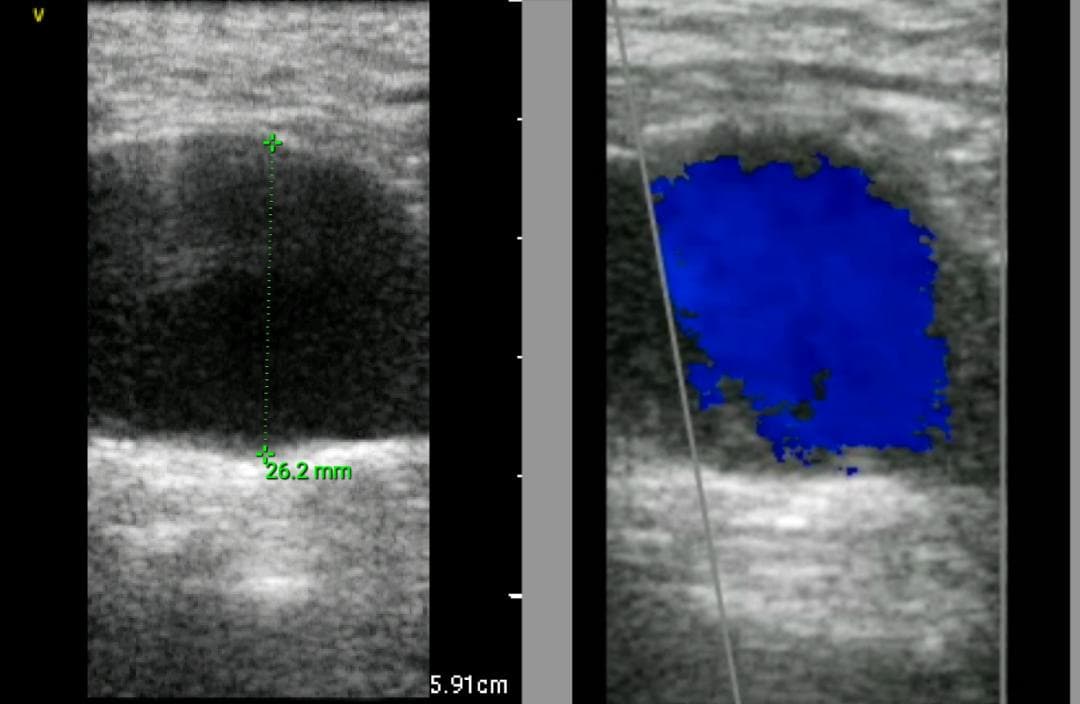

おわかりになる方のみの購入をお願いいたします実際に実施した写真をあげました正常肝臓、胆石症、頸動脈プラーク、同じく頸動脈プラーク、Mrの収縮期、同じくM弁の開放期とA弁の開放期、腹部大動脈瘤、正常の頸動脈、甲状腺右葉の結節、前立腺肥大画像の描出は条件によりますがご検討をお願いいたします経年変化、使用に伴うスレや傷などがあります機能に問題はありませんスキャンは心血管、腹部、体表に対応します外部接続端子のカバーが一部壊れていますが蓋は閉まりますバッテリーはフル充電されますが劣化はあると思います医療用モニタリング機器 Vscan Extend、GE- モデル名: Vscan Extend- ブランド: GE- 色: ホワイト- 機能: 医療用モニタリング機器ご覧いただきありがとうございます。鈴木 ALCARE Youcare-TDc 医療用テープ 25mm 6個。